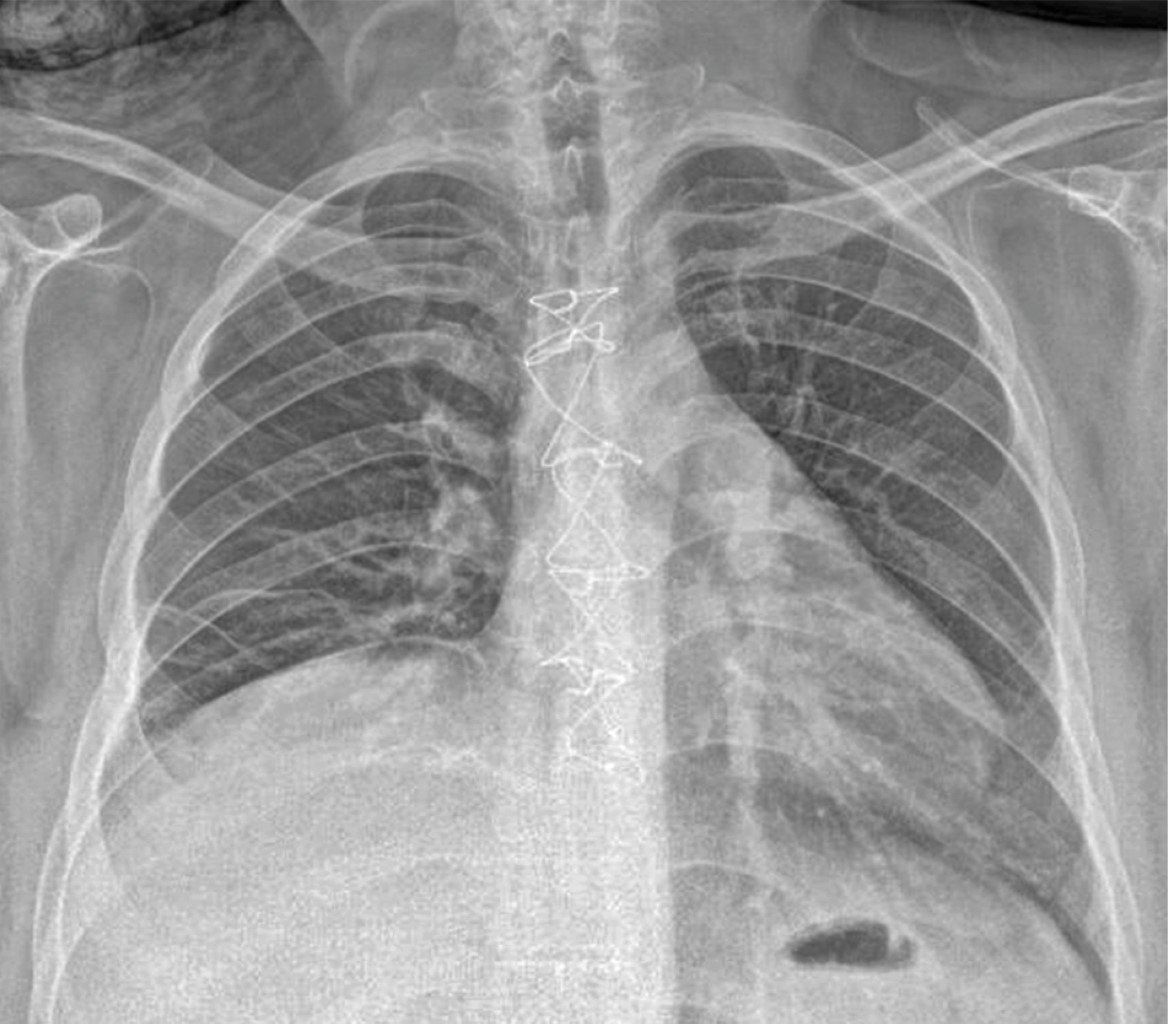

Imaging studies' role is vital in diagnosis, without neglecting a thorough clinical history and physical examination. The main findings in the plain chest x-ray raise the suspicion of DNM and the clinical signs and symptoms of severe infection associated with a history of cervical, dental, or oropharyngeal infection. Said radiological findings can be widening of the mediastinum, pneumomediastinum, mediastinal hydro-aerial levels, anterior displacement of the tracheal air column due to a prevertebral opacity of the soft tissues, enlargement of the cardiac silhouette and loss of the normal lordosis of the cervical spine, as well as unilateral or bilateral pleural effusion.9,10,12 Cervicothoracic computed tomography (CT) should be performed immediately, as CT of the chest and neck can reveal detailed information regarding the extent of the necrosis process and suggests, within the framework of the surgical treatment approach, the best tactic for effective drainage to optimize the best post-surgical outcome for the patient and with it the need for fewer reinterventions.9,10,13-17

In our series, chest radiography continues to be the initial study in all patients with respiratory problems due to its accessibility and quick results (Figure 1); however, chest tomography continues to be the gold standard at our institution for the diagnosis and planning of surgical management in those with mediastinitis (Figure 2).